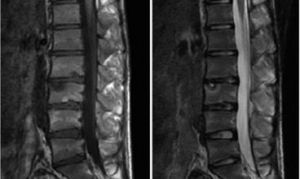

駝背為主要症狀,伴脊柱強直。頸常屈曲、肩下垂、胸廓狹窄而扁、肩胛骨突出。疼痛並不嚴重,常為隱痛。駝背畸形進行性發展至20歲之後。X線表現 ①椎體上、下前方邊緣有不規則的凹痕,環形骨骺相應部位的形態與大小不均勻並與椎體分離;②多個椎體前方呈楔形變,伴Schmorl結節;③椎間隙輕度狹窄;④胸椎或胸腰段後突畸形超過正常的25°~40°;⑤成年後在椎體前緣早期出現骨關節炎性骨刺.